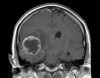

| | |  |  | Defeat of the Evil Glioma After months of worrying and weighing options decisions were made, and on Wednesday I was fully resigned to reality.